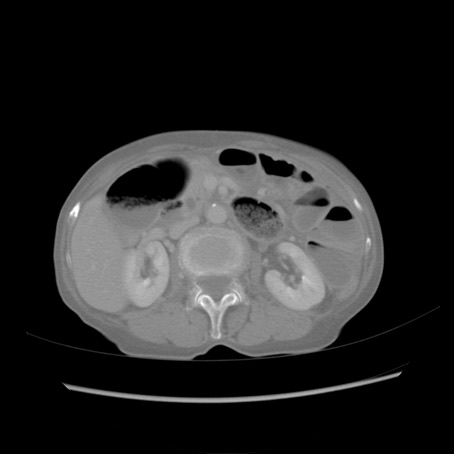

冠状断像

【症例】80歳代女性

【主訴】胸のつかえ感

【現病歴】約9時間前に食後から胸のつかえた感じあり、嘔吐あり、来院。

【既往歴】胃癌(全摘)、胆摘、虫垂炎

【身体所見】心窩部に圧痛あり、反跳痛なし。

【データ】WBC 5700、CRP 0.05